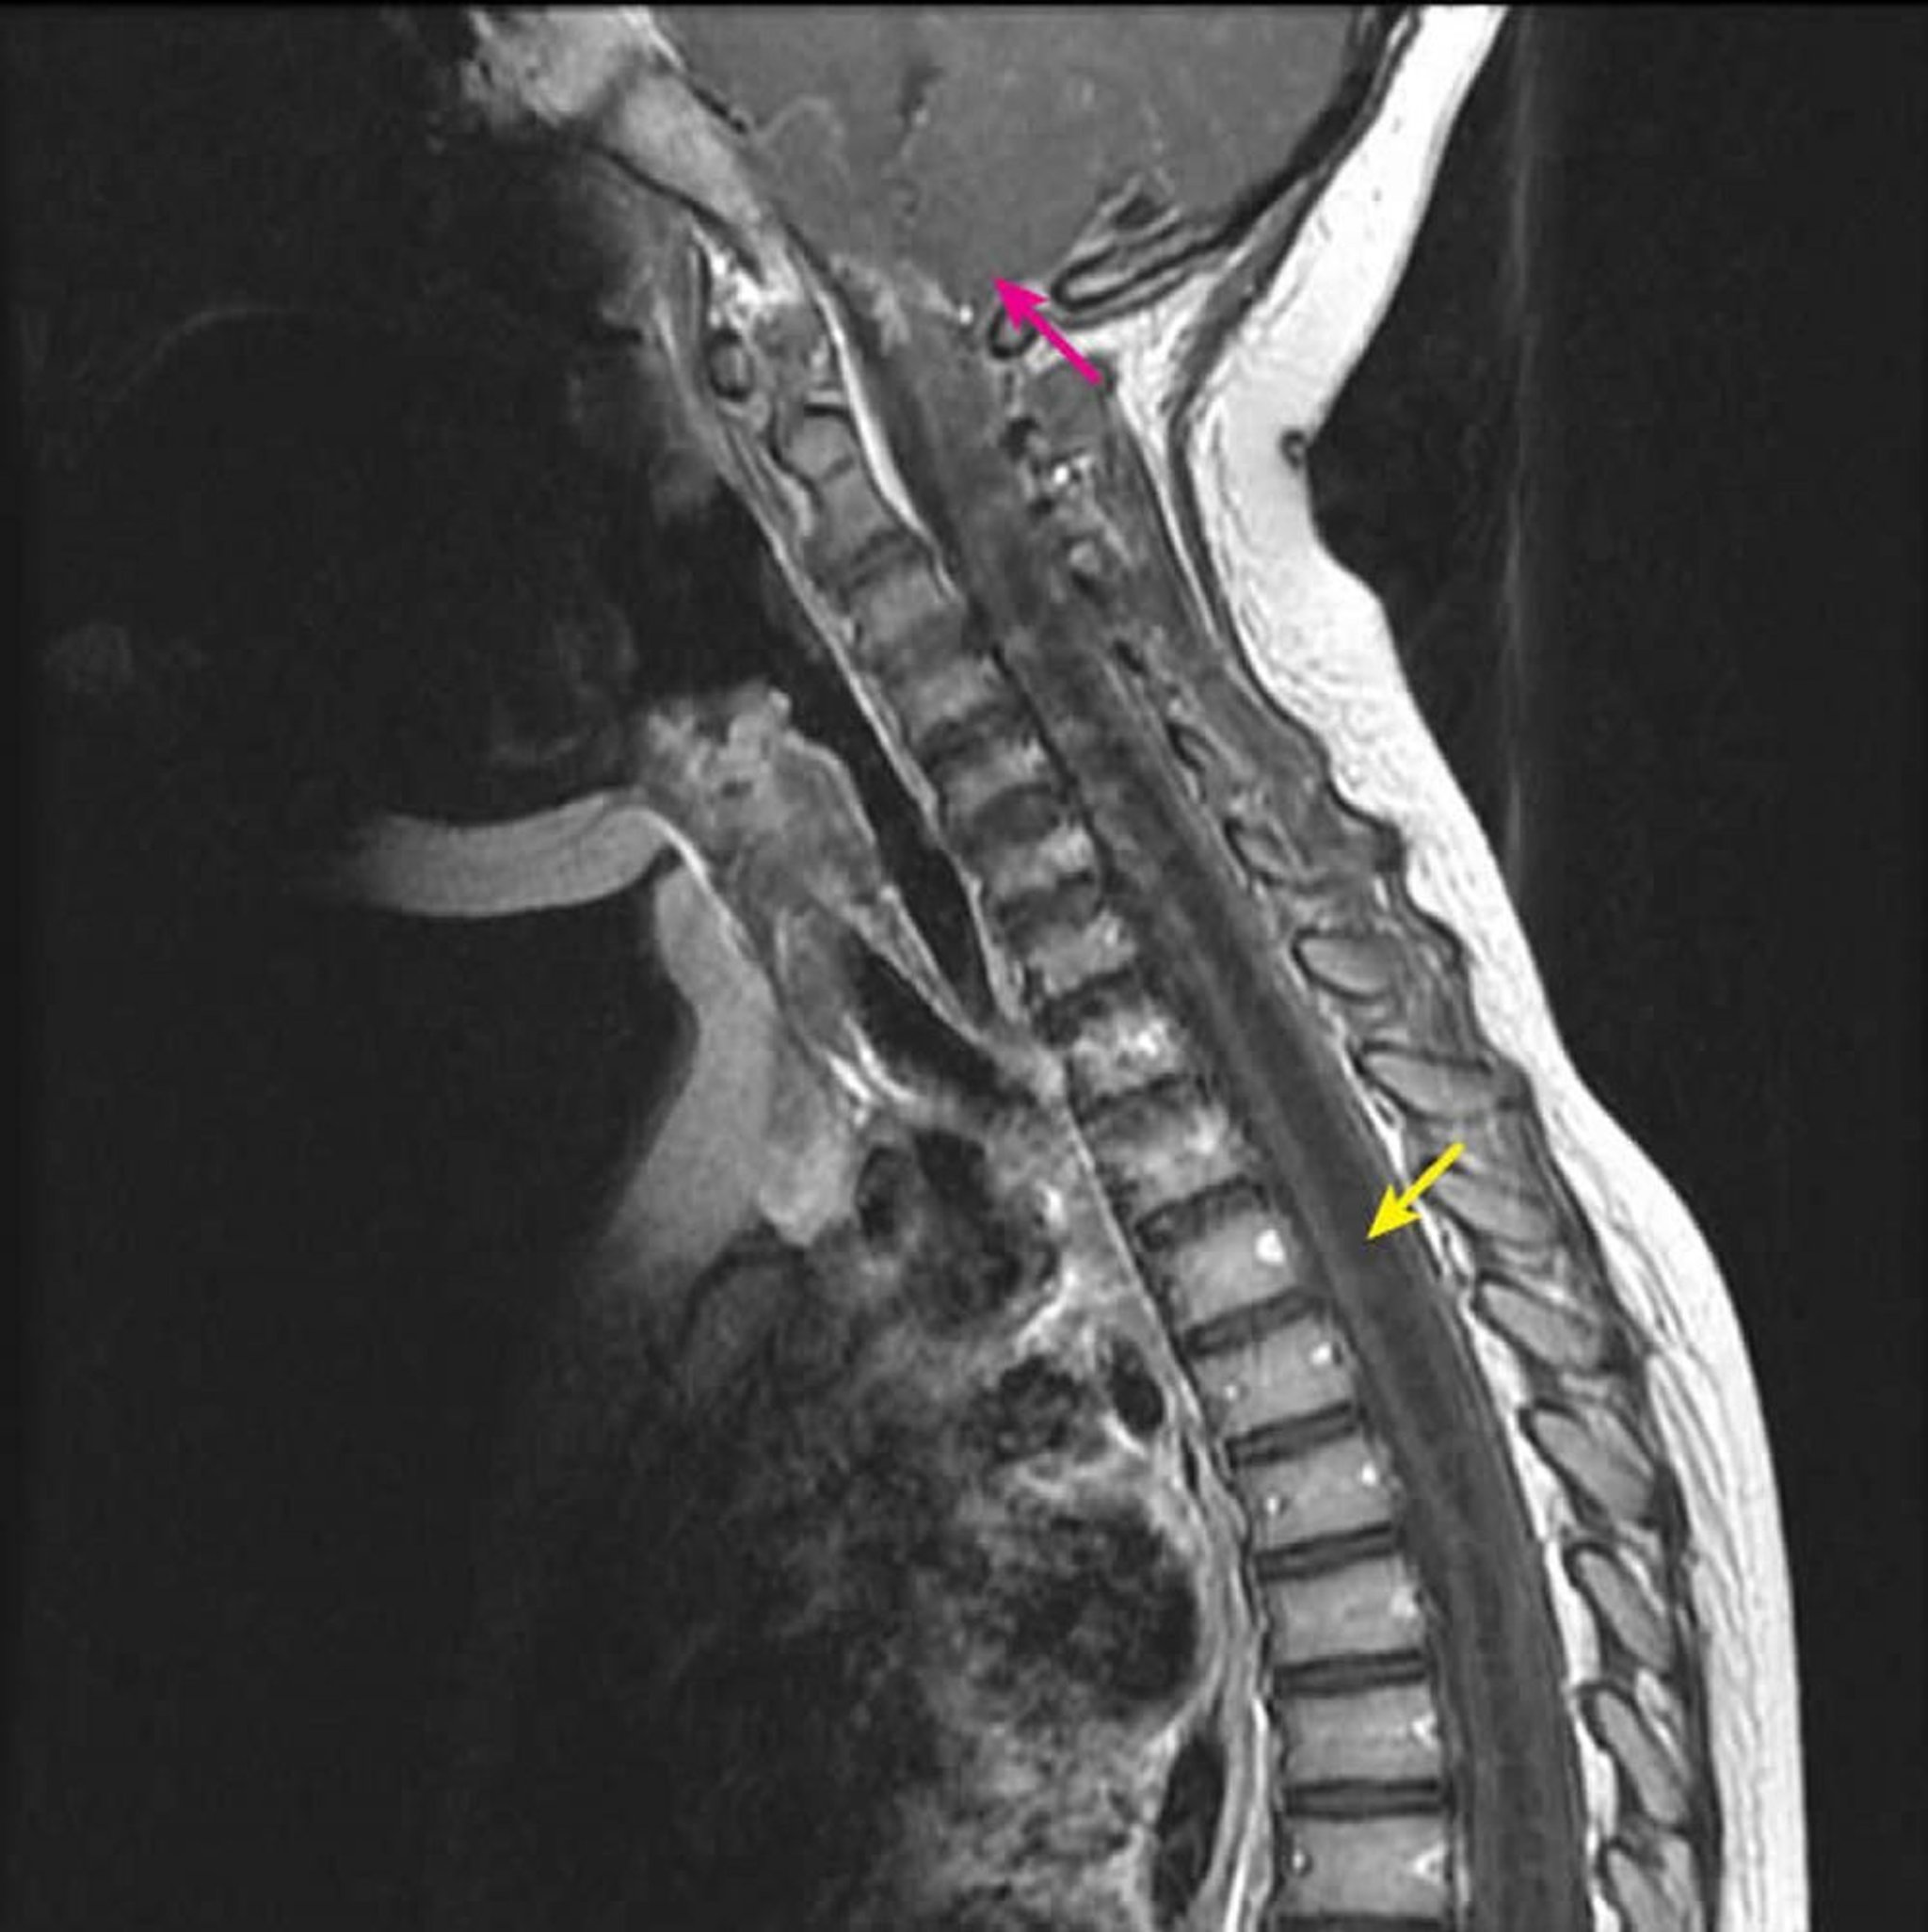

Siringoidromielia cervico-toracica

La RM pesata in T1 post-contrasto mostra una grande cavità del midollo spinale intramidollare ipointensa in T1 caratteristica di una siringomielia (freccia gialla). Si estende dal livello cervicale C2-C3 inferiormente in un bambino con una malformazione di Chiari I già diagnosticata (freccia rosa). Questo quadro è definito come siringoidromelia perché la siringomielia (una cavità eccentrica del midollo spinale) non può essere differenziata dall'idromielia (una cavità centrale del midollo spinale) mediante imaging.

Courtesy of John Tsiouris, MD, Division of Neuroradiology, New York–Presbyterian Hospital/Weill Cornell Medical Center.